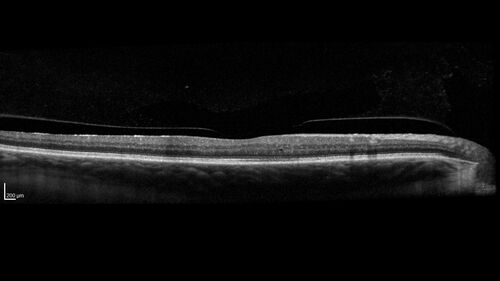

Choroidal Melanocystosis

65 year old female with normal vision.